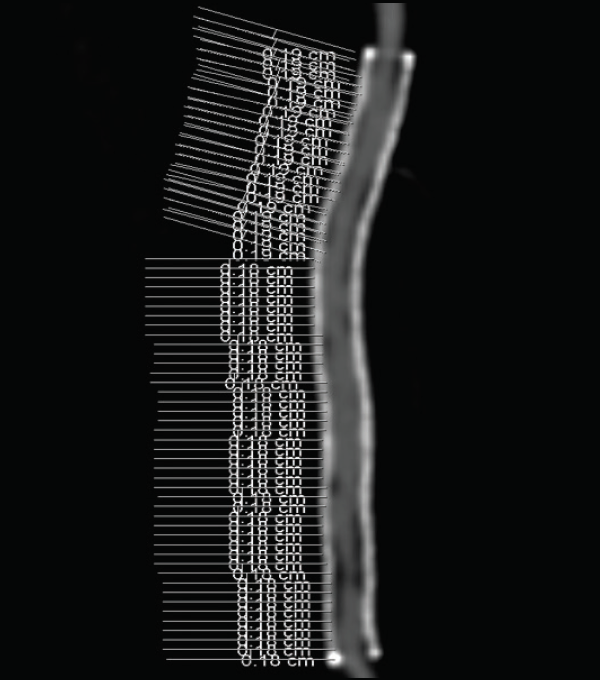

Comparison of High Versus Low Chronic Outward Force Nitinol Stents in

Comparison of High Versus Low Chronic Outward Force Nitinol Stents in Nitinol Force nitinol metal, also known as nickel titanium, is a type of shape memory alloy that exhibits extraordinary flexibility and resilience. nitinol, a unique alloy of nickel and titanium, has garnered attention for its remarkable properties. the mechanical and shape memory properties shown here are typical for standard shape memory nitinol at room. in the many practical. Nitinol Force.

Comparison of High Versus Low Chronic Outward Force Nitinol Stents in Nitinol Force nitinol, a unique alloy of nickel and titanium, has garnered attention for its remarkable properties. the mechanical and shape memory properties shown here are typical for standard shape memory nitinol at room. nitinol metal, also known as nickel titanium, is a type of shape memory alloy that exhibits extraordinary flexibility and resilience. in the many practical. Nitinol Force.